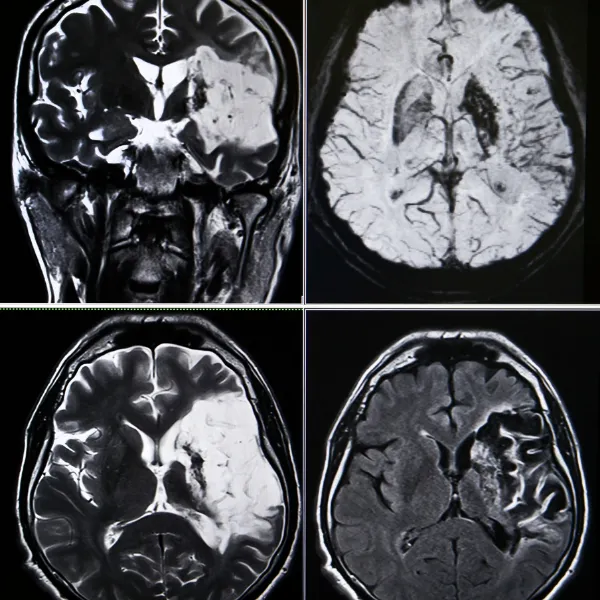

A stroke occurs when the brain suddenly loses access to the blood and oxygen it needs. This can happen in two ways:

- A blocked blood vessel, known as an ischemic stroke

- A ruptured blood vessel, known as a hemorrhagic stroke

Because strokes directly affect the brain, neurologists play an important role in determining what type of stroke occurred, what part of the brain is affected, and what steps are needed to protect long-term function.

Advanced diagnostic tools help us understand what’s happening inside the brain and blood vessels. At CNS, we offer in-office testing such as EEG, EMG, nerve conduction studies, and ultrasound (TCD) to evaluate brain activity, nerve function, and cerebral blood flow. These tests allow us to detect subtle changes early and take action before a stroke occurs.